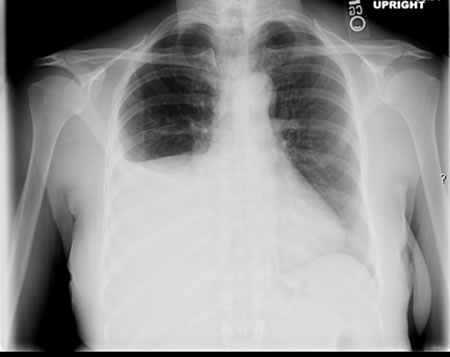

Pulmonary tuberculosis

Right-sided pleural effusion

From the personal collection of David Horne and Masahiro Narita; used with permission